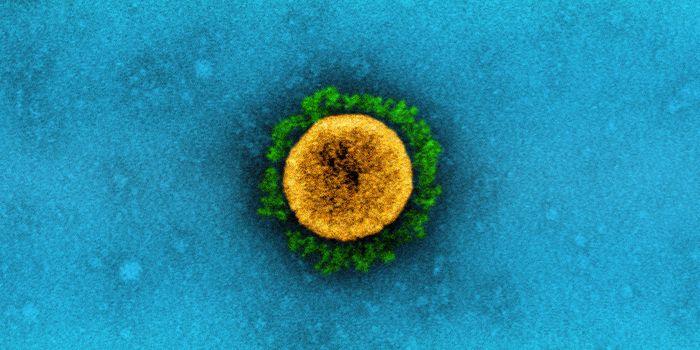

MAR 22, 2020MicrobiologyMore data is being gathered from an unfortunate and dramatic rise in the number of COVID-19 cases around the world.

APR 01, 2020MicrobiologyThere are a couple of different kinds of tests that researchers will be developing and clinicians will be using to disru ...

MAY 03, 2020Genetics & GenomicsThe origin of SARS-CoV-2, the pandemic virus that causes COVID-19, has become politicized as leaders seek to place blame ...

JUL 06, 2020MicrobiologyThe pandemic coronavirus has caused a wide range of different symptoms, and as time goes on, we may find that it can hav ...

JUL 05, 2020Cell & Molecular BiologyThe pandemic virus SARS-CoV-2 enters the body through the respiratory system to cause the illness COVID-19. But we know ...

JUN 29, 2020MicrobiologyVaccines that contain live attenuated viruses may be giving people some protection from serious cases of COVID-19 that i ...

FEB 22, 2021MicrobiologyReporting in Science, researchers have created an antiviral nasal spray that could help us get the COVID-19 pandemic und ...

SEP 01, 2021MicrobiologyIt's been generally assumed that people who get infected with SARS-COV-2 will develop antibodies to the virus, which cau ...